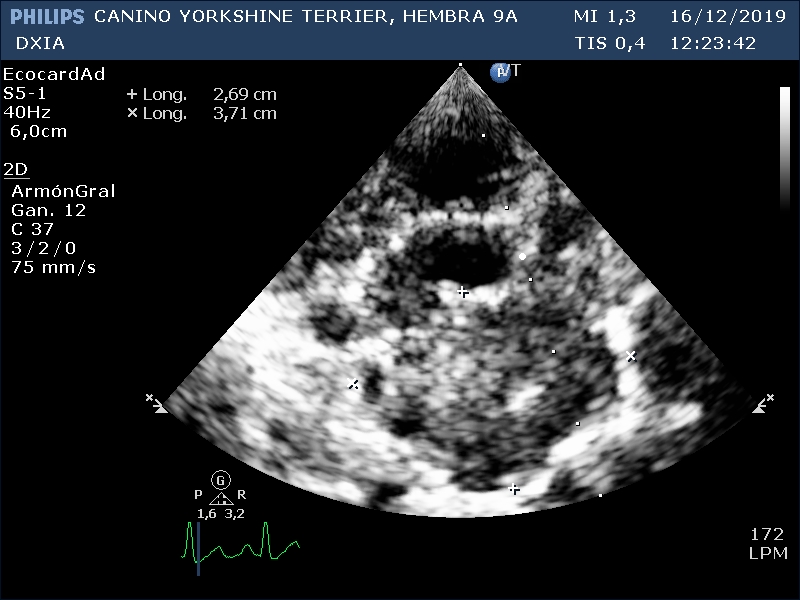

Corte en base cardíaca izquierda: Estructura hipoecogénica heterogénea compatible con posible tumor en base cardíaca.

Corte oblicuo a nivel de la base cardíaca